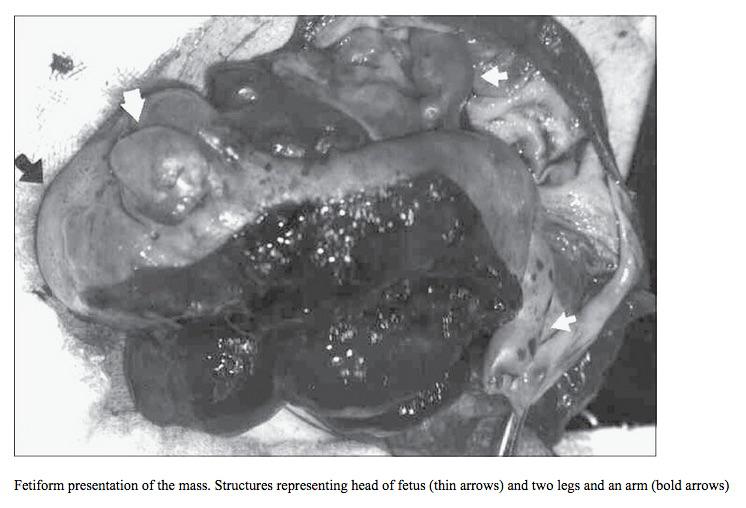

L’opération dure trois heures, au terme de laquelle ils extraient, avec stupeur, non pas un kyste, mais un fœtus « fossilisé », doté d’un visage, d’un œil, d’une dent et d’une longue chevelure brune, semblable à celle de Jenny Kavanagh. En fait, il s’agit là de son jumeau, qui, pendant 45 ans, s’est développé à l’intérieur d’elle.

Le fœtus in fetu, lui, présente déjà une organisation telle que l’on peut y observer des vertèbres, des membres ou encore des tissus organiques (dents, ongles, cheveux...). Il se nourrit de son environnement (en l’occurrence, un ovaire), mais, bien sûr, il n’a ni cœur battant, ni sang circulant.

Source : Journal of Indian Association of Pediatric Surgeons, Janv-Mars 2008

Pour Jenny Kavanagh, la nouvelle a été difficile à encaisser, notamment parce que le fœtus était particulièrement développé. A son réveil, les chirurgiens lui ont montré une photo de la masse extraite. « Je me suis sentie triste quand je l’ai vu, parce qu’il a presque la taille et le poids d’un bébé. Le fait qu’il ait des longs cheveux comme moi (…) a renforcé cette impression. Mais je me dis qu’il m’aurait très probablement tuée si on ne me l’avait pas retiré ». A tout moment, le fœtus risquait en effet de se décrocher.